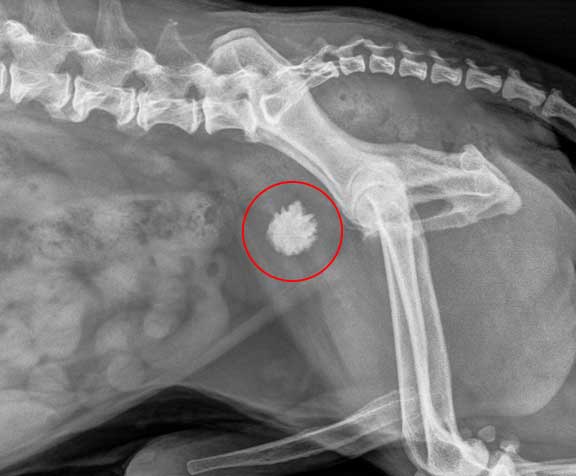

요로결석증

신장, 요관, 방광, 요도 중에 결석이 생기는 질병이에요

소형견의 경우 큰 결석이 생기면 방광 근처를 만졌을 때 단단한

응어리가 느껴지게 되는데요 요도 결석은 소변을 볼 때마다 통증을 일으키고

배뇨포즈를 취해도 나오지 않게 됩니다. 결석이 요로를 막아버린 경우에는

가능한 빨리 수술을 통해 제거하고 재발 방지를 위해 반드시 식이요법을 해야합니다.